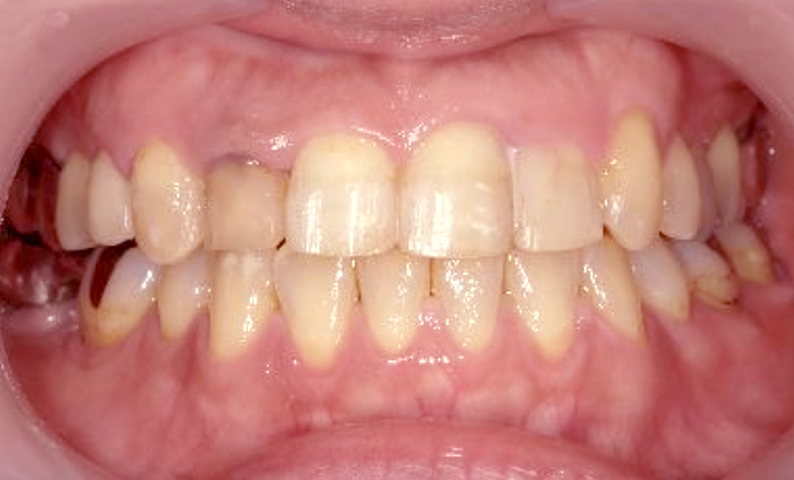

症例_003 上下顎の部分矯正

治療期間:12ヶ月金額:54万円+税男性八重歯前歯のガタガタ

| Before | After |

|---|---|

|